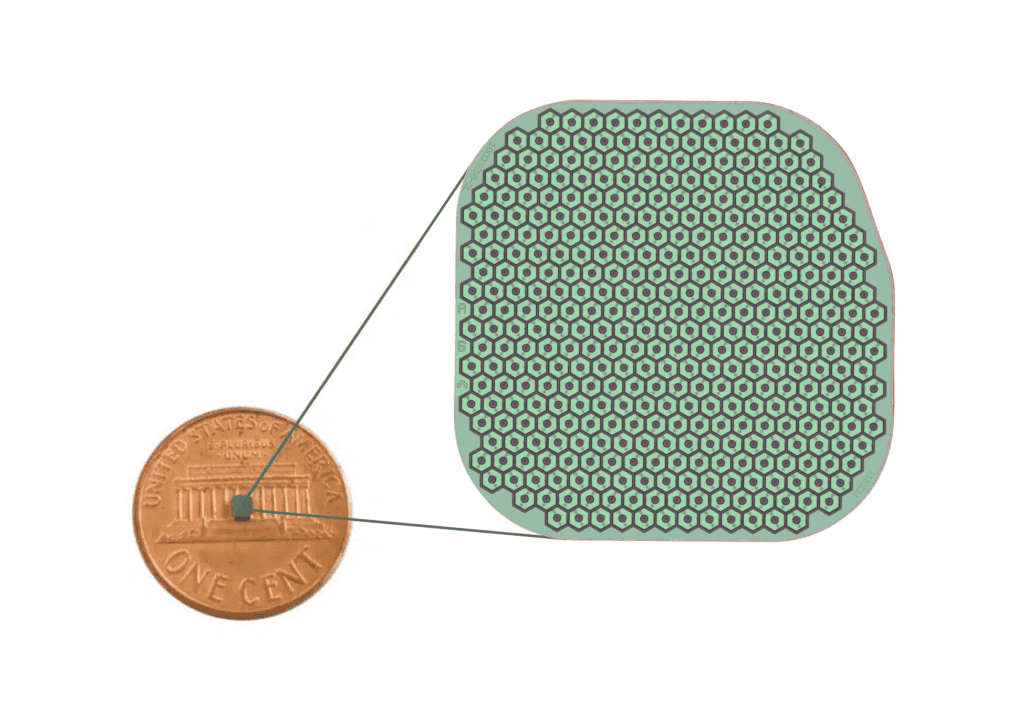

ชิป Prima ประกอบด้วยชิปสี่เหลี่ยมจัตุรัสขนาด 2 มม. ที่ถูกผ่าตัดวางไว้ใต้จอประสาทตา ตรงส่วนหลังสุดของลูกตา โดยใช้เวลาผ่าตัดนานถึง 80 นาที โดยจะใช้งานร่วมกับแว่นตาพร้อมกับกล้องที่จะบันทึกภาพ และส่งแสงอินฟราเรดไปยังชิป แล้วชิปดังกล่าวจะทำหน้าที่เสมือนแผงโซลาร์เซลล์ขนาดเล็ก ที่จะแปลงแสงเป็นการกระตุ้นไฟฟ้า และส่งไปยังสมอง จากนั้นสมองจะตีความสัญญาณดังกล่าวเป็นภาพ ซึ่งเป็นการเลียนแบบกระบวนการการมองเห็นตามธรรมชาติ

ในโรคจอประสาทตาเสื่อมตามวัย เซลล์เฉพาะทางที่เรียกว่าโฟโตรีเซพเตอร์เซลล์ (Photoreceptor cell) จะได้รับความเสียหายเมื่อเวลาผ่านไป โฟโตรีเซพเตอร์เซลล์ซึ่งอยู่บริเวณด้านหลังของจอประสาทตาจะแปลงแสงให้เป็นสัญญาณที่ส่งไปยังสมอง “ถึงแม้ว่าโฟโตรีเซพเตอร์จะใช้การไม่ได้ แต่จอประสาทตาจะยังคงอยู่เป็นส่วนใหญ่ ในแนวทางของเรา อิมแพลนต์จะเข้ามาแทนที่โฟโตรีเซพเตอร์” Daniel Palanker, ศาสตราจารย์ด้านจักษุวิทยาที่มหาวิทยาลัยสแตนฟอร์ด ผู้ประดิษฐ์อิมแพลนต์ Prima กล่าว